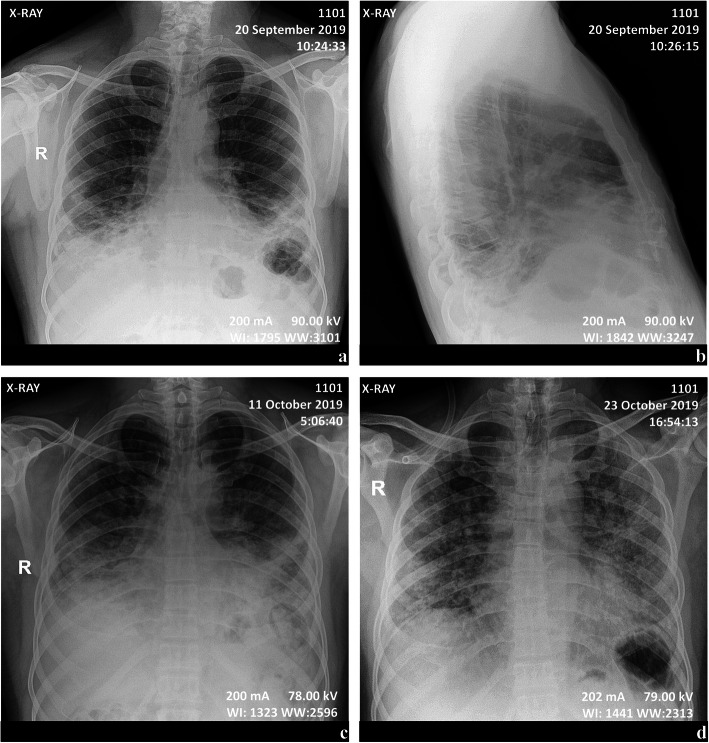

Fig. 1.

Serial chest X-rays of Patient 1. Multifocal then diffuse airspace disease in a 55-years-old man. Bibasal lung consolidation with assorted trabeculae, especially in the posterior regions, overhung by discreet hazy opacities (a, b). Follow-up showing a cranially progress of the predominant inhomogeneous consolidation still coexisting with a clearly diffuse ground-glass (c). There is apparent replacement of alveolar densification by diffuse reticular interstitial marks with some few parahilar nodules (d)

A 55-year-old man, with a 10-year history of hypertension (treated with nicardipine 20 mg twice daily, bisoprolol 5 mg twice daily and aldactazine 1 tablet once daily) and a 5-year history of pigeon breeding, was seen in the Department of Internal Medicine on September 20, 2019, for dry cough, 2 weeks after returning from Guangzhou (Guangdong province, China). The patient did not complain of any loss of smell or taste. He had good mental orientation. Axillary temperature was 37 °C. Chest auscultation noted normal heart sounds and normal vesicular breath sounds without rales or sibilance. There was no abdominal tenderness nor enlarged liver or spleen. There was no low limb oedema. There was no loss of peripheral motor or sensor function and no other abnormal neurological signs. Laboratory results showed normal complete blood count (CBC) and procalcitonin (< 0.1 ng/ml); an elevated serum creatinine (1.8 mg/dl, hence a glomerular filtration rate, GFR, of 50.6 ml/(min*1.73m2)) and electrolytes disturbances (low sodium at 130 mmol/l, low potassium at 3.4 mmol/l and low calcium 1.04 mmol/l) (Table 1). A diagnosis of non-specific interstitial pneumonia was evoked based on chest X-rays showing bi-basal and posterior densification (25 to 30% of total chest height), blurring heart borders and diaphragm, associated with trabecular bands and ground-glass zones on the mid third of the lungs (Fig. 1a, b). He was sent back home with oral azithromycin (500 mg daily for 5 days), paracetamol (1000 mg up to 3 times a day if necessary) and an antitussive drug.

Despite treatment, coughing was exacerbated, and fever and dyspnoea occurred 2 weeks later. On October 10, 2019, he was admitted in the Emergency ward. The clinical evaluation noticed polypnea (30 breaths/min), tachycardia (100 beats/min) and fever (38 °C). Oxygen saturation (SaO2) measured with a pulse oximeter was 54% [normal range: 95–100%]. The patient presented a respiratory distress (nose flaring, chest retractions and cyanosis) and had fine crackles at both lung bases. Cardiovascular examination was normal. Laboratory results showed a moderate inflammatory syndrome with hyperleukocytosis (11,600 leucocytes/μl [4000-10,000/μl] of which 9071 neutrophils [1500-7000/μl] and 1380 lymphocytes [1500-4500/μl]) and increased C-reactive protein (CRP, 54.9 mg/l [0–3 mg/l]). Procalcitonin levels were normal [below 0.1 ng/ml]. An arterial blood gas (ABG) analysis revealed the presence of severe hypoxemia (PaO2 33 mmHg [75–100 mmHg], SaO2 74%) and respiratory alkalosis (pH 7.55 [7.35–7.45], PaCO2 29.7 mmHg [35–45 mmHg], PaO2/FiO2 ratio 157 mmHg [400–500 mmHg], bicarbonate 25.1 mmol/l [22–26 mmol/l], and lactates 1.89 mmol/l [< 2 mmol/l]). Bacteriological investigations were all negative. Tuberculosis was unlikely given a Ziehl-Neelsen stain of sputum which was negative for three samples collected at different times. HIV serological tests were negative (Table 1). A second chest X-rays showed persistence of the aforementioned findings, except for the trabeculae hidden by the alveolar densification that had progressed up to the level of the main bronchi, overhung by a well delimited ground glass zone without encroachment upon the apices (Fig. 1c).

Four days later, no improvement was observed. The oxygen flow was increased to 10 l/min and dexamethasone replaced by methylprednisolone (125 mg twice daily for 5 days). During the following week, there was a slight improvement of the dyspnoea and fever, but on October 23, 2019, fever reappeared, and the respiratory distress worsened. A new chest X-ray showed a reduction of the alveolar consolidation to the advantage of an interstitial syndrome (reticulations, ground-glass, and nodules ≤6 mm) extending to lung tops (Fig. 1d). Meanwhile, the CRP was 49 mg/l and procalcitonin 0.62 ng/ml. A diagnosis of respiratory zoonosis was considered, given the history of pigeon breeding. Intravenous methylprednisolone (125 mg twice daily) was reintroduced and Duovent® (combined ipratropium and fenoterol) was administered in nebulization, without any improvement. SaO2 (measured with a pulse oximeter) remained at 40%, PaO2/FiO2 ratio decreased to less than 70 mmHg, and the patient became confused, with loss of notion of space and time, probably because of the hypoxia.